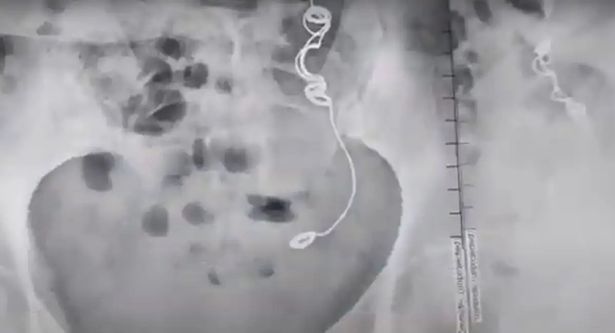

而且,每次到城生看医生,花费并不小,对她而言是极大负担。直到2022年11月,终于有医生认为她的症状十分诡异,而要求进行核磁共振与超音波检查,结果在她体内发现手术用的针线。

当医生问起以前是否曾动过手术时,她才想起10年前的结扎手术。

艾德琳达确定病因后,直接找到当初替她结扎的医生,没想到对方却否认自己出现这种医疗疏失的可能,甚至暗指艾德琳达自己将针线吞下肚。

目前她仍在等候医生的评估,以确定是否可以再次动手术将异物取出。